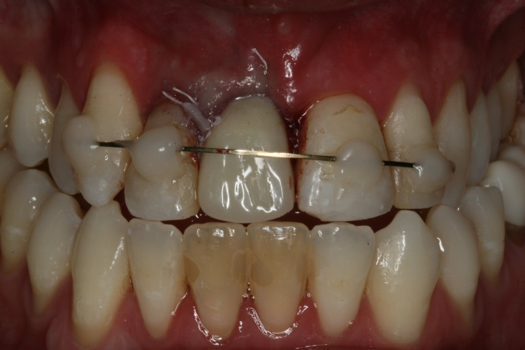

A 23-year-old man reported to the dental practice on January 3. Apparently, while on vacation and celebrating the New Year, the patient experienced a loss of equilibrium and found himself horizontal in the crosswalk. When surveying the damages, his friends noticed he was missing tooth No. 8. Those who were involved were not able to find the missing maxillary central incisor. The young man was eventually seen about 3 days after the trauma. A CBCT radiograph, study models, and photographs were collected, and teeth Nos. 6 through 10 were immobilized with composite and 20 x 20 orthodontic wire (Figure 14). The CBCT and photos were emailed to the dental laboratory, and the analog intraoral impression with a centric occlusion bite registration was sent via ground transportation. Due to the nature of the trauma, the laboratory and the author expeditiously converted the analog diagnostics and merged all the patient's data sets to develop the plan. Based on the 3D data sets, the laboratory and the dentist were able to accurately assess the volume of bone and soft tissue remaining after the trauma. The volume was still intact and soft tissue was plentiful (Figure 15 and Figure 16).

Fig 14. Immobilization splint placed 3 days after trauma.

Figure 14